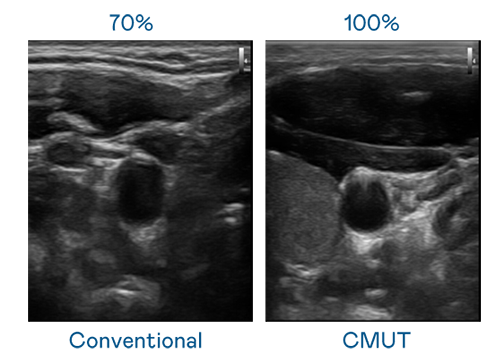

CMUT 技术是一种用电容式微机电元件来产生超音波讯号的技术。与传统 PZT 压电式技术相比,CMUT 频宽增加 30%,更宽频的超音波讯号让影像解析度大幅提升,是实现高影像品质医疗超音波扫描、促进精准医疗发展的关键技术。

大频宽带来超清晰影像

超音波影像的解析度高低,首先取决于探头能发出的讯号频宽。ag真人国际官网 CMUT 可提供高清晰的超音波讯号,提供高频宽、高灵敏度、影像纹理细节更高的超音波影像,协助医护人员缩短影像判读时间及利用精准的医疗影像进行诊断。